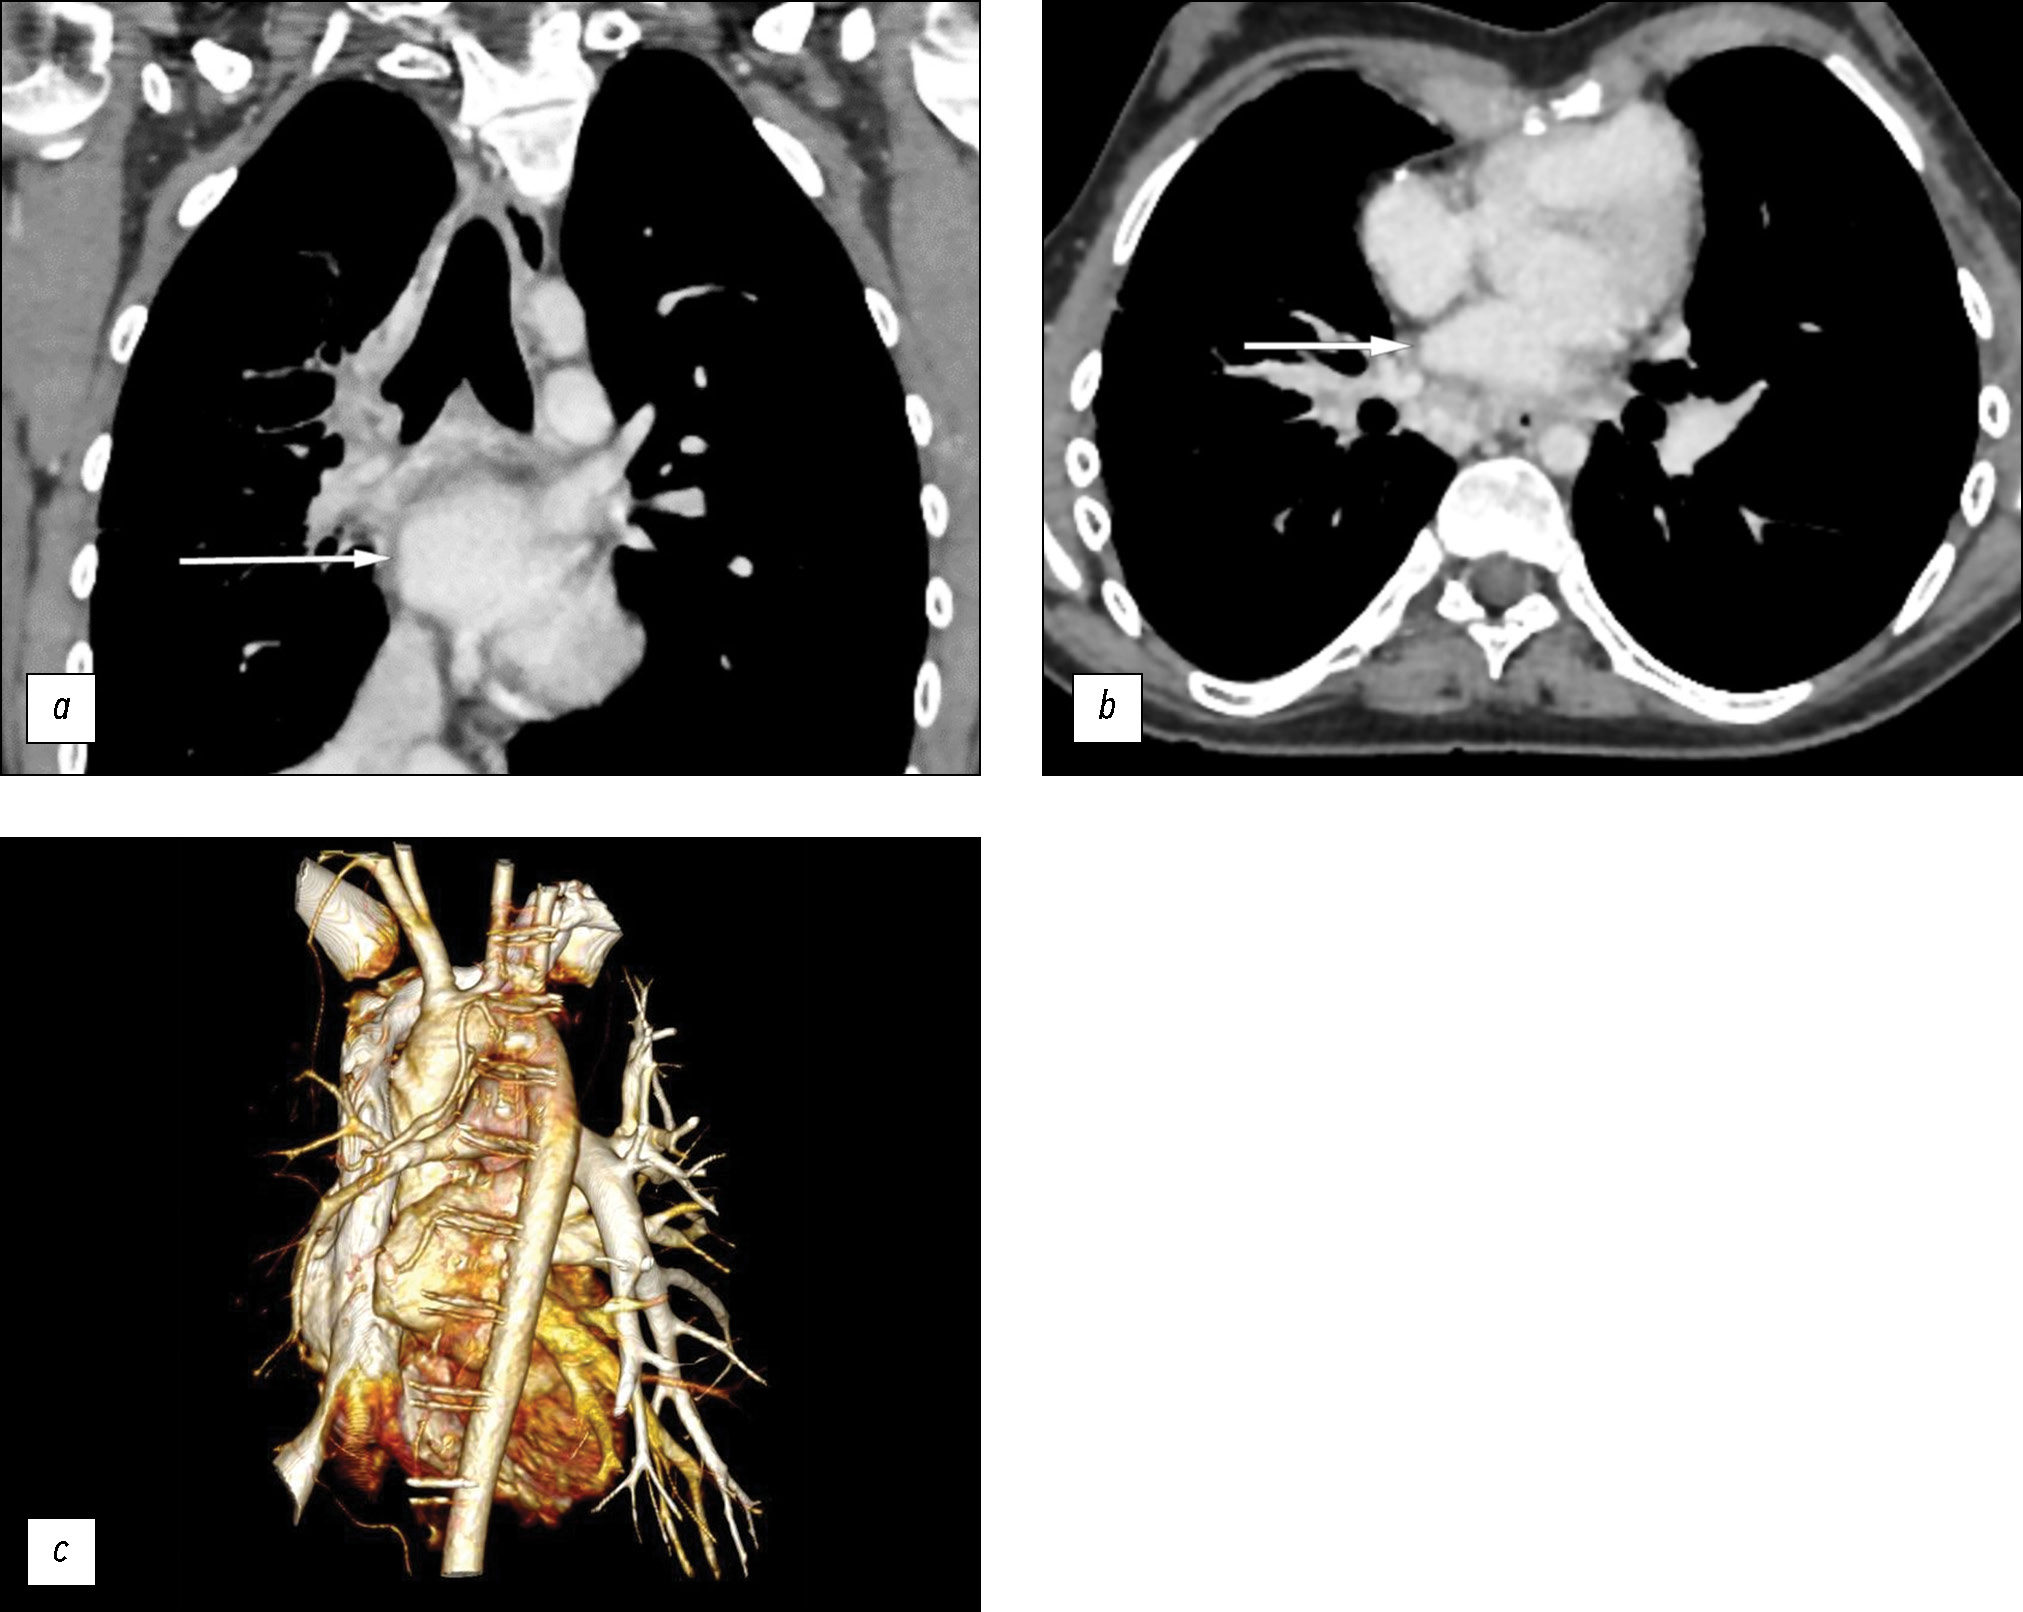

Arterial and venous phase scanning along the margins of the right main bronchus revealed multiple dilated, tortuous arterial and venous vessels (bronchial and intercostal) in the intrathoracic lymph nodes; without contrast enhancement, they were previously interpreted as manifestations of intrathoracic lymphadenopathy (Fig. 3). The decreased diameter of the right pulmonary artery to 7 mm (vs. 14 mm on the contralateral side) and absence of contrast enhancement in the right pulmonary veins were clearly visualized in the three-dimensional reconstruction of the heart (Fig. 4).

Fig. 3. Computed tomography of the lungs; (a, b) axial plane; c: coronal plane. White arrows: multiple vascular collaterals along the bronchial contour. Black arrow: hypoplasia of the right pulmonary artery.

Fig. 4. Absence of the right pulmonary veins (white arrows); (a) computed tomography of the lung in the coronal plane; (b) computed tomography of the lung in the axial plane; (c) three-dimensional reconstruction of the heart.